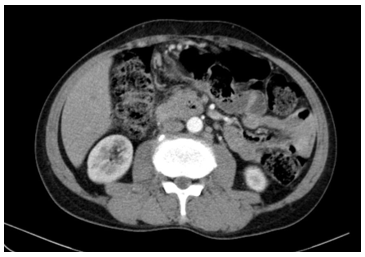

• CT bụng tiêm thuốc cản quang: Hình ảnh nốt ngấm thuốc gan trái. Sỏi nhỏ thận phải. Nang thận hai bên.

Hình 2. Hình ảnh nốt ngấm thuốc gan trái, không còn thấy hạch dọc động mạch chủ bụng (sau điều trị)

Sau điều trị 6 đợt hóa chất, bệnh nhân cải thiện rõ về mặt lâm sàng với giảm kích thước hạch ngoại vi và không còn đau vùng hạch bẹn phải,cẳng chân phải đỡ sưng nề và tê bì. Trên hình ảnh học, kích thước hạch cổ, bẹn và ổ bụng giảm rõ, không còn ghi nhận hạch động mạch chủ bụng, tổn thương nhu mô gan không tiến triển. Phác đồ được dung nạp tương đối tốt, độc tính chủ yếu ở mức độ nhẹ đến trung bình. Bệnh nhân được tiếp tục theo dõi.